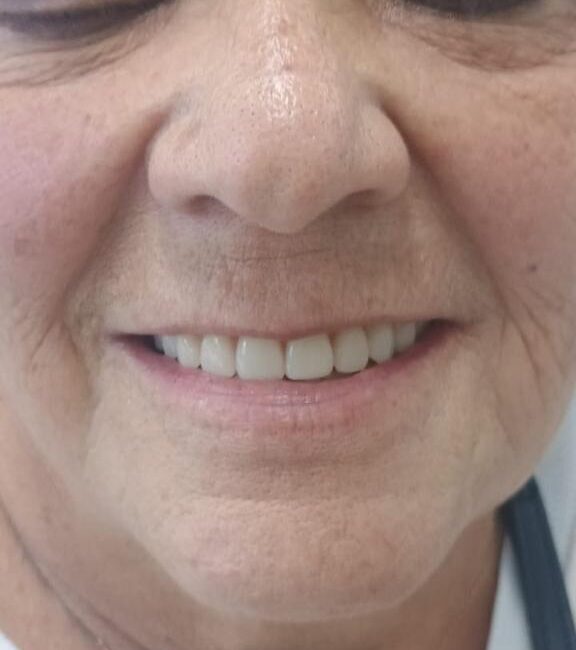

– Reabilitação Rápida: Permite a colocação de próteses fixas em um único procedimento cirúrgico.

– Estética Imediata: Os pacientes podem sair da clínica com um sorriso restaurado no mesmo dia.

3. Colocação da Prótese: Instalação de uma prótese fixa imediatamente após a colocação dos implantes.